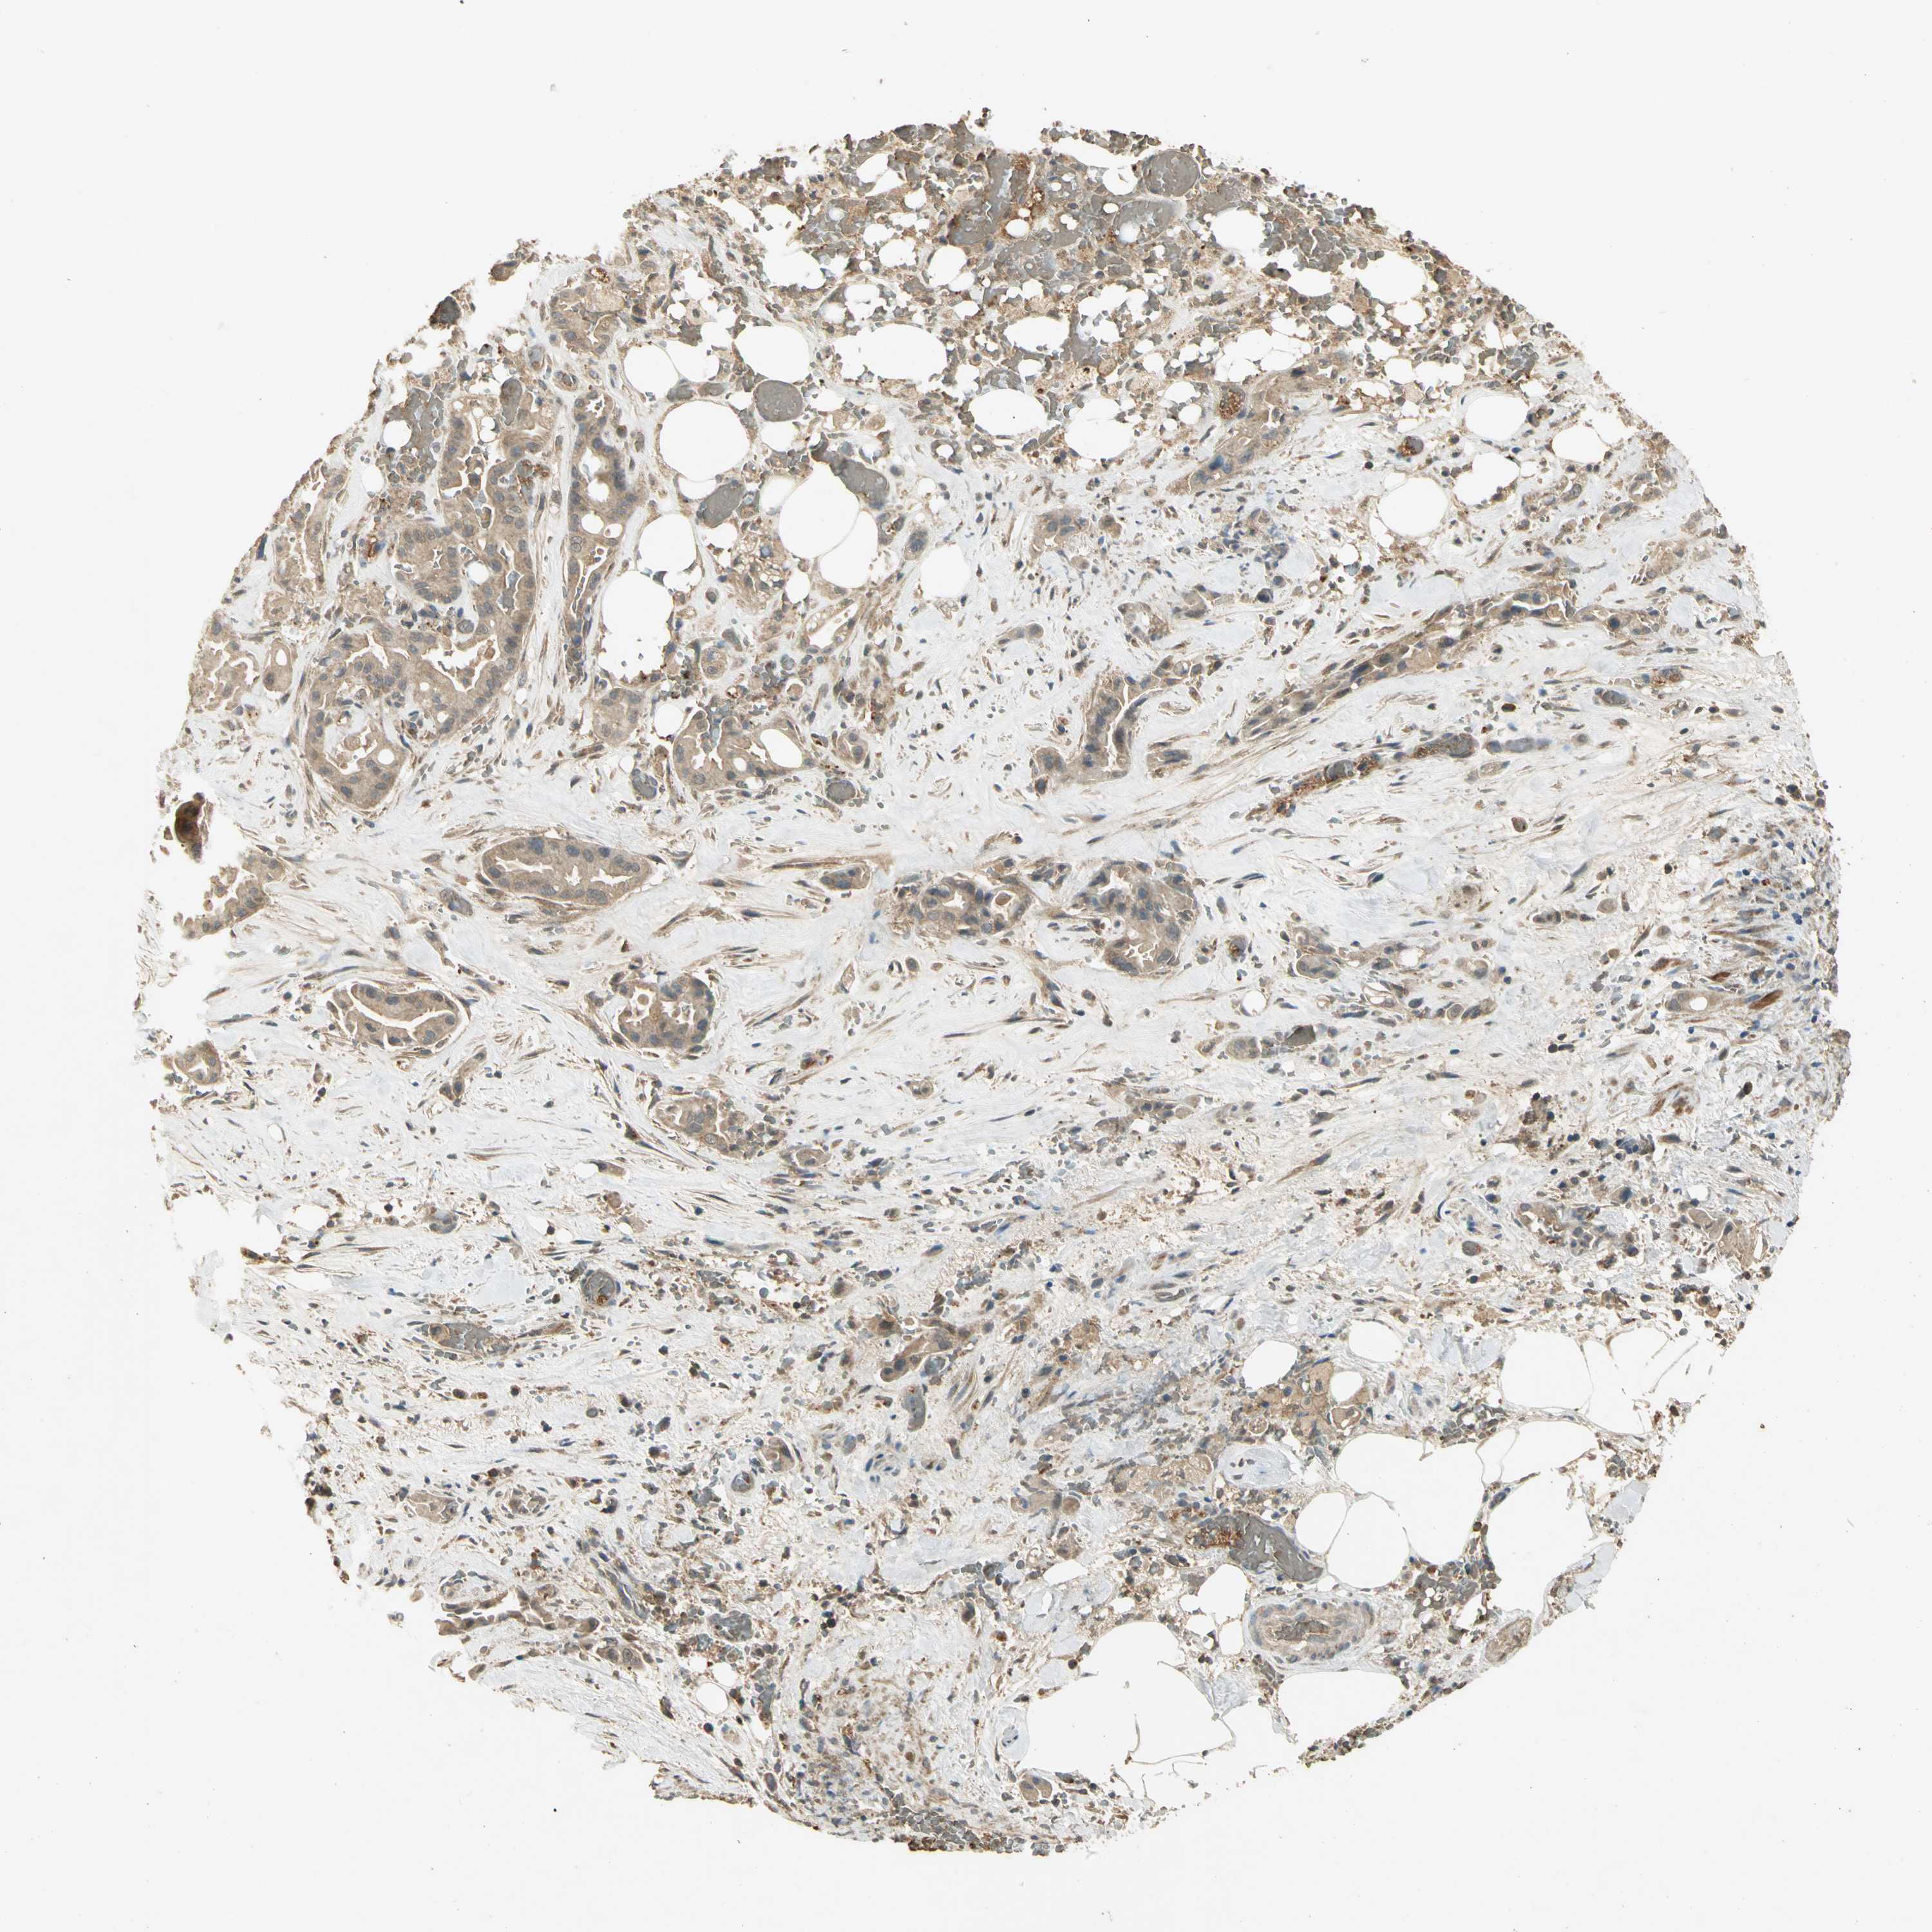

LIVER CANCER - Protein expressioni

A mouse-over function shows sample information and annotation data. Click on an image to view it in a full screen mode. Samples can be filtered based on level of antibody staining by selecting one or several of the following categories: high, medium, low and not detected. The assay and annotation is described here.

Note that samples used for immunohistochemistry by the Human Protein Atlas do not correspond to samples in the TCGA dataset.

Antibody stainingi

Antibody staining in the annotated cell types in the current human tissue is reported as not detected, low, medium, or high, based on conventional immunohistochemistry profiling in selected tissues. This score is based on the combination of the staining intensity and fraction of stained cells.

Each image is clickable and will lead to virtual microscopy that enables deeper exploration of all samples and also displays staining intensity scores, fraction scores and subcellular localization as well as patient and tissue information for each sample.

Antibody HPA005558

Antibody CAB025337

Staining

High

Medium

Low

Not detected

Intensity

Strong

Moderate

Weak

Negative

Quantity

>75%

75%-25%

<25%

None

Location

Nuclear

Cytoplasmic/membranous

Cytoplasmic/membranous,nuclear

Cholangiocarcinoma

Carcinoma, Hepatocellular, NOS